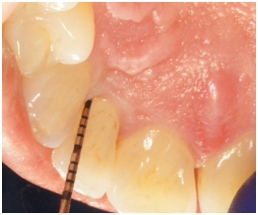

A 72 year-old white male was referred due to an isolated increasing probing depth on the disto-facial aspect of the mandibular right lateral incisor which had an initial PD of 10 mm with BOP (Table 2). Increase in probing depth is illustrated in the clinical photo (Figure 6). The patient was seen for a comprehensive periodontal examination and a periodontal maintenance visit after scaling and root planing was previously performed. His oral hygiene and plaque control was very good and no local factors were detected at that time. Radiographic evaluation revealed a slight radiolucency on the distal of tooth #26 (Figure 7).

Figure 6 Pretreatment clinical photo of tooth #26 with distal facial PD of 10mm.